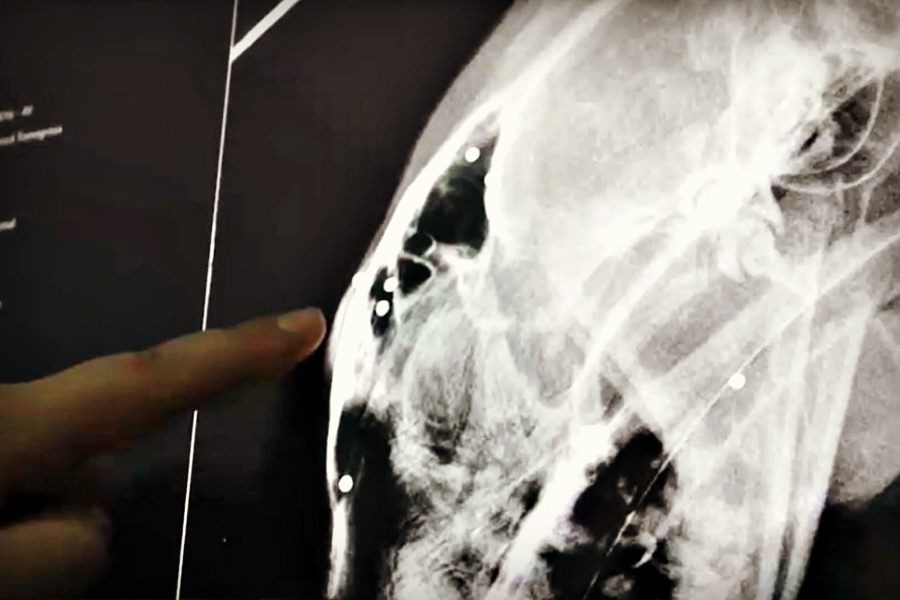

Hasta siete rastros de postones en la cabeza de un puma logró contabilizar la Dra. Natalia Durán, veterinaria clínica del Zoológico Nacional, quien analizó las radiografías que dan cuenta de este triste y preocupante hallazgo.

Y eso fue sólo en su cabeza, porque en el resto del cuerpo hay más perdigones. Factor que indica que fueron dañados por terceros. Por eso la importancia de la rehabilitación, cuando se encuentra un puma por las calles.